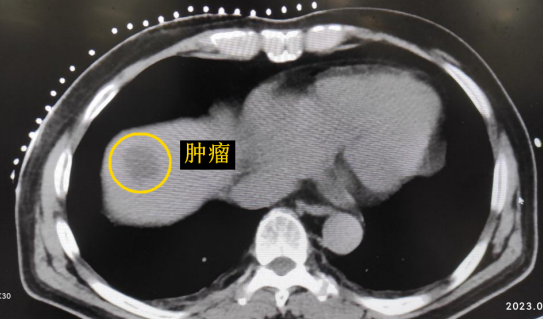

患者老年男性,曾于2021年行結(jié)腸癌手術(shù)。幾月前,發(fā)現(xiàn)肝臟轉(zhuǎn)移瘤,但沒有干預(yù)。近期CT顯示該轉(zhuǎn)移瘤明顯增大,并發(fā)現(xiàn)另一處轉(zhuǎn)移灶。

影像診療科陳寶瑩主任團(tuán)隊評估后指出,較大的腫瘤位于肝頂部緊貼膈肌,如果繼續(xù)發(fā)展,腫瘤很可能突破肝包膜侵犯到膈肌,建議及時干預(yù)。病變緊臨膈肌,如果要完全消融,膈肌損傷的可能性就比較大,與其他局部治療方式比較,冷凍消融對周圍臟器、血管及神經(jīng)損傷的可能性較小、安全性更高、患者疼痛感較輕,建議通過CT精準(zhǔn)引導(dǎo)下經(jīng)皮微創(chuàng)冷凍消融治療。

CT精準(zhǔn)定位腫瘤